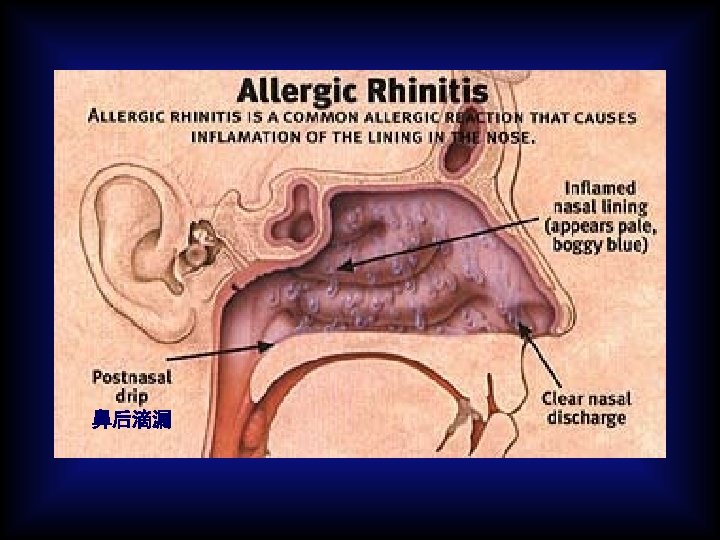

Pathology: Type allergy Allergic inflammation: Predominant T cells & eosinophilic cells infiltrate.

Symptoms & Signs: Nasal irritation and iching recurrent attacks of paroxysmal sneezing copious watery rhinorrhea nasal obstruction